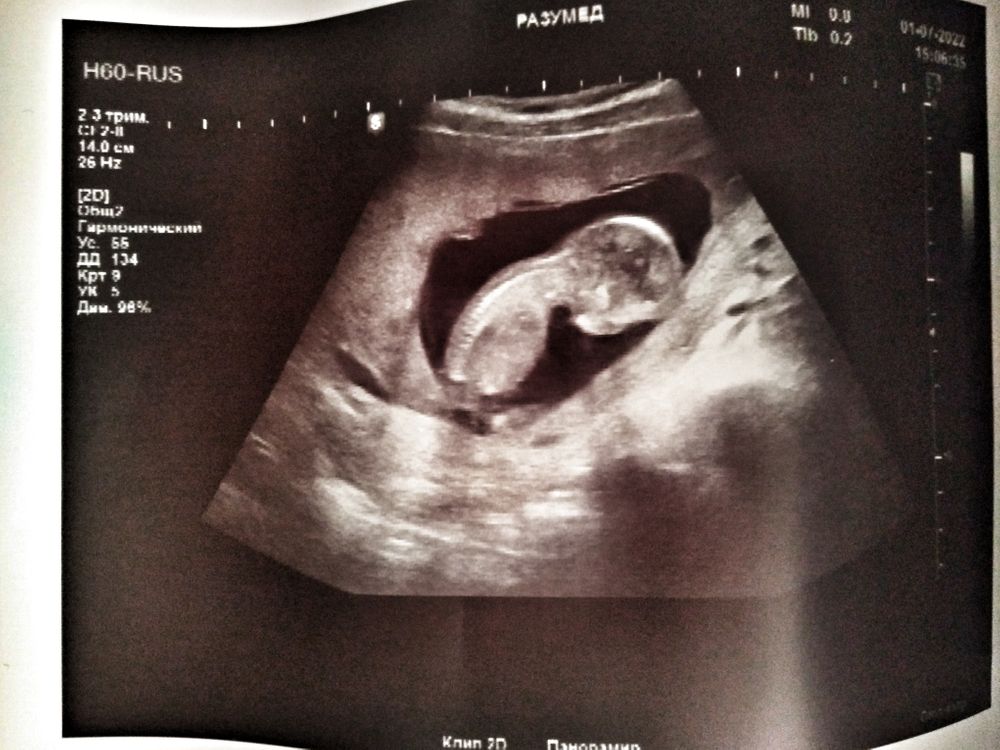

Здесь не видно полового бугорка) пусть главное будет здоров или здорова 🥰